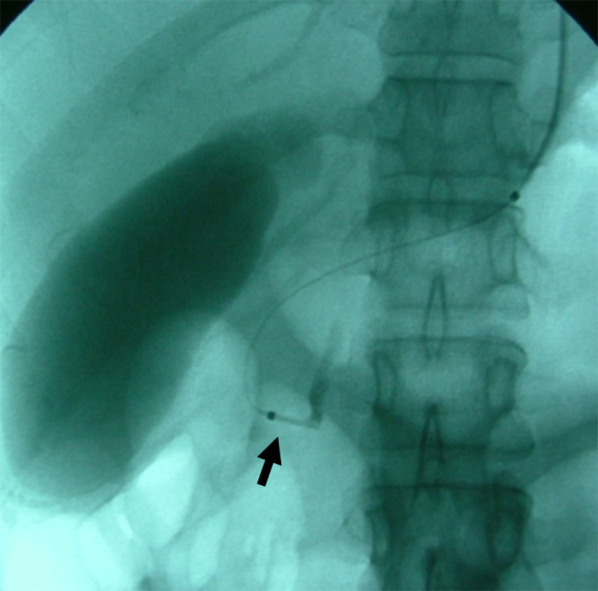

A 30-year-old woman was transported to our hospital by ambulance due to epigastric pain. A laboratory analysis revealed the following: white blood cells, 4000/mm3; total bilirubin, 3.0 mg/dL; alkaline phosphatase, 640 IU/L; GOT, 395 IU/L; GPT, 746 IU/L; and amylase, 37 IU/L. Abdominal CT demonstrated multiple gallbladder (GB) stones without inflammation of the GB; the diameter of the common bile duct (CBD) was 10 mm. ERCP was performed under the suspicion of CBD stones. Bile duct cannulation was easily performed. Cholangiography revealed no apparent CBD stones. Although EBD is not routinely carried out in this situation, we carefully performed EBD due to the suspicion of CBD stones, and carefully taking the clinical course into consideration. Before the procedure, a dilatation balloon (Hurricane RX Rapid Exchange, Boston Scientific, MA, USA) was inflated as a precaution in order to check the condition of the balloon. The dilatation balloon was then passed over the guidewire and located at the site of the biliary sphincter. The balloon was inflated to 2 atmospheres of pressure. After the procedure, the balloon suddenly burst. We were unable to remove the EBD catheter because the balloon was caught at the biliary sphincter (Figs. 1, 2). A computed tomography (CT) scan showing the burst balloon located at the site of the biliary sphincter (Fig. 3). Finally, we had to perform surgical intervention to remove the EBD. We made an incision at the pylorus, and then we manually pulled the EBD catheter through this incision, as shown in Fig. 4a, b. The broken catheter was successfully removed without injuring the biliary sphincter. Cholecystectomy, CBD exploration, and then removal of the CBD stone were performed. A T-tube was inserted for drainage. Intra-operative cholangiography revealed no residual stones and no biliary sphincter abnormality (Fig. 5). The burst balloon of the EBD catheter is shown in Fig. 6. The patient was discharged without any complications after removal of the T-tube on post-operative day 14.